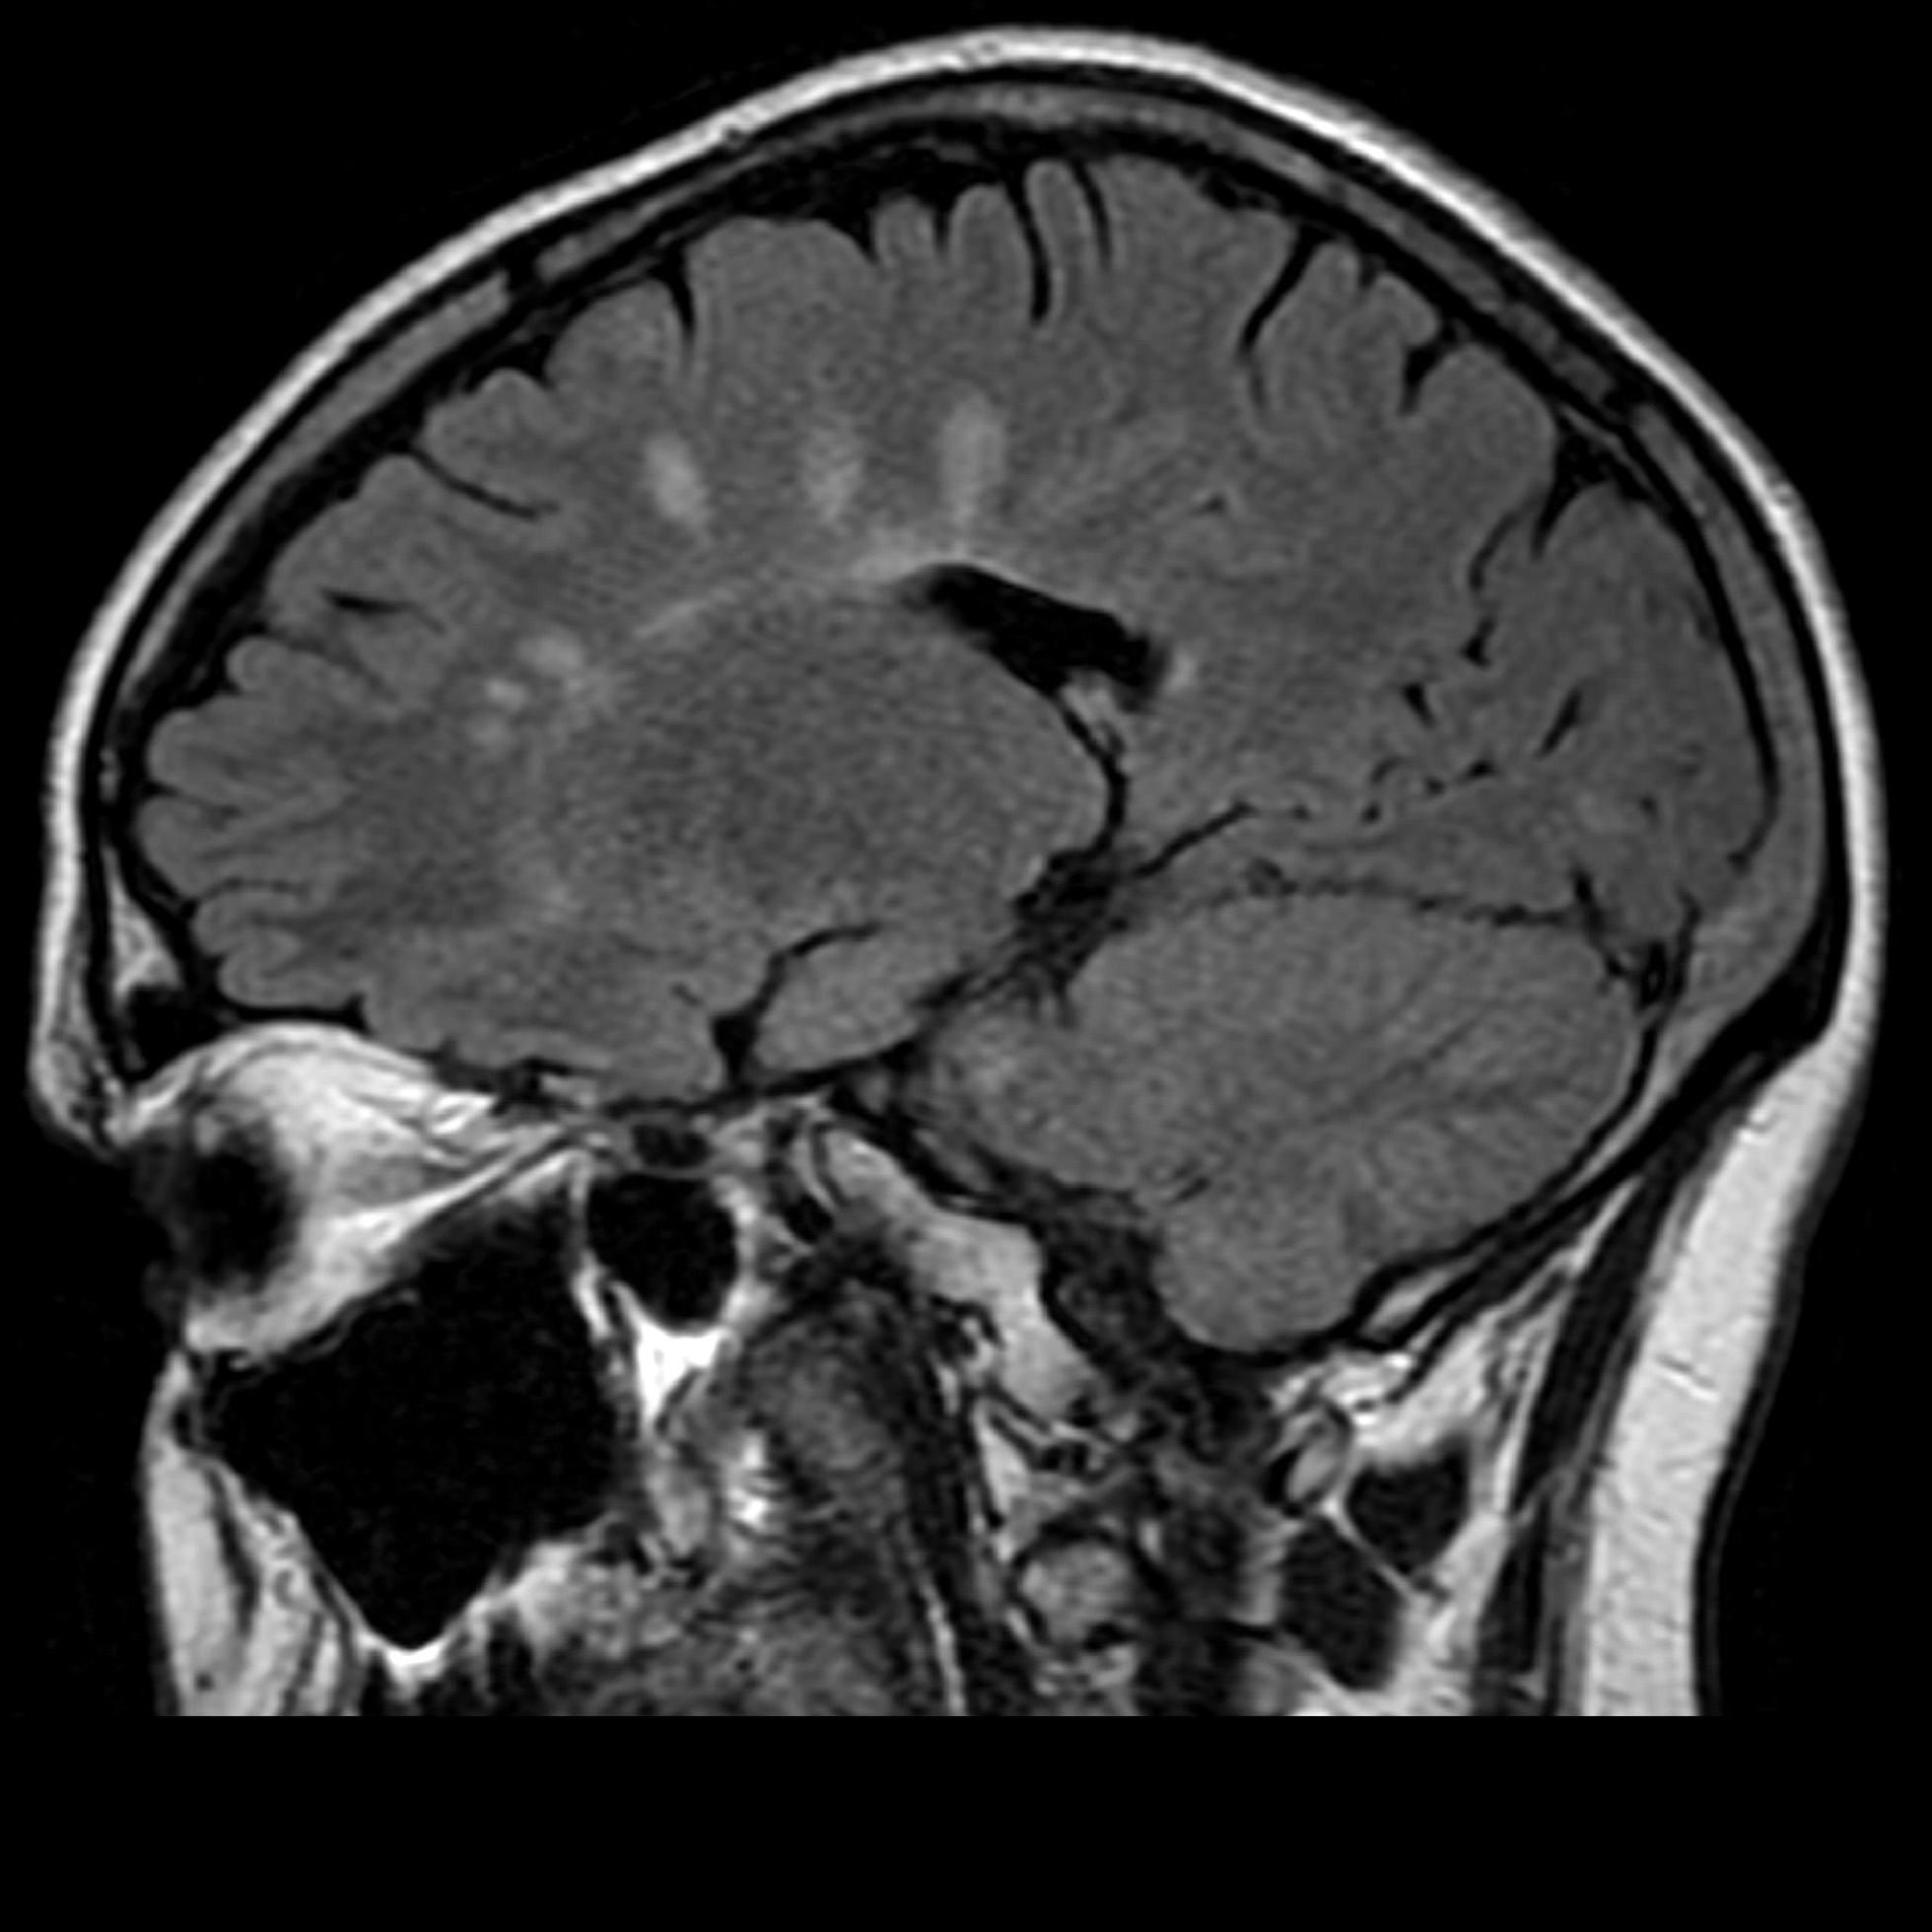

Демиелинизирующие заболевания мозга: МРТ изображения